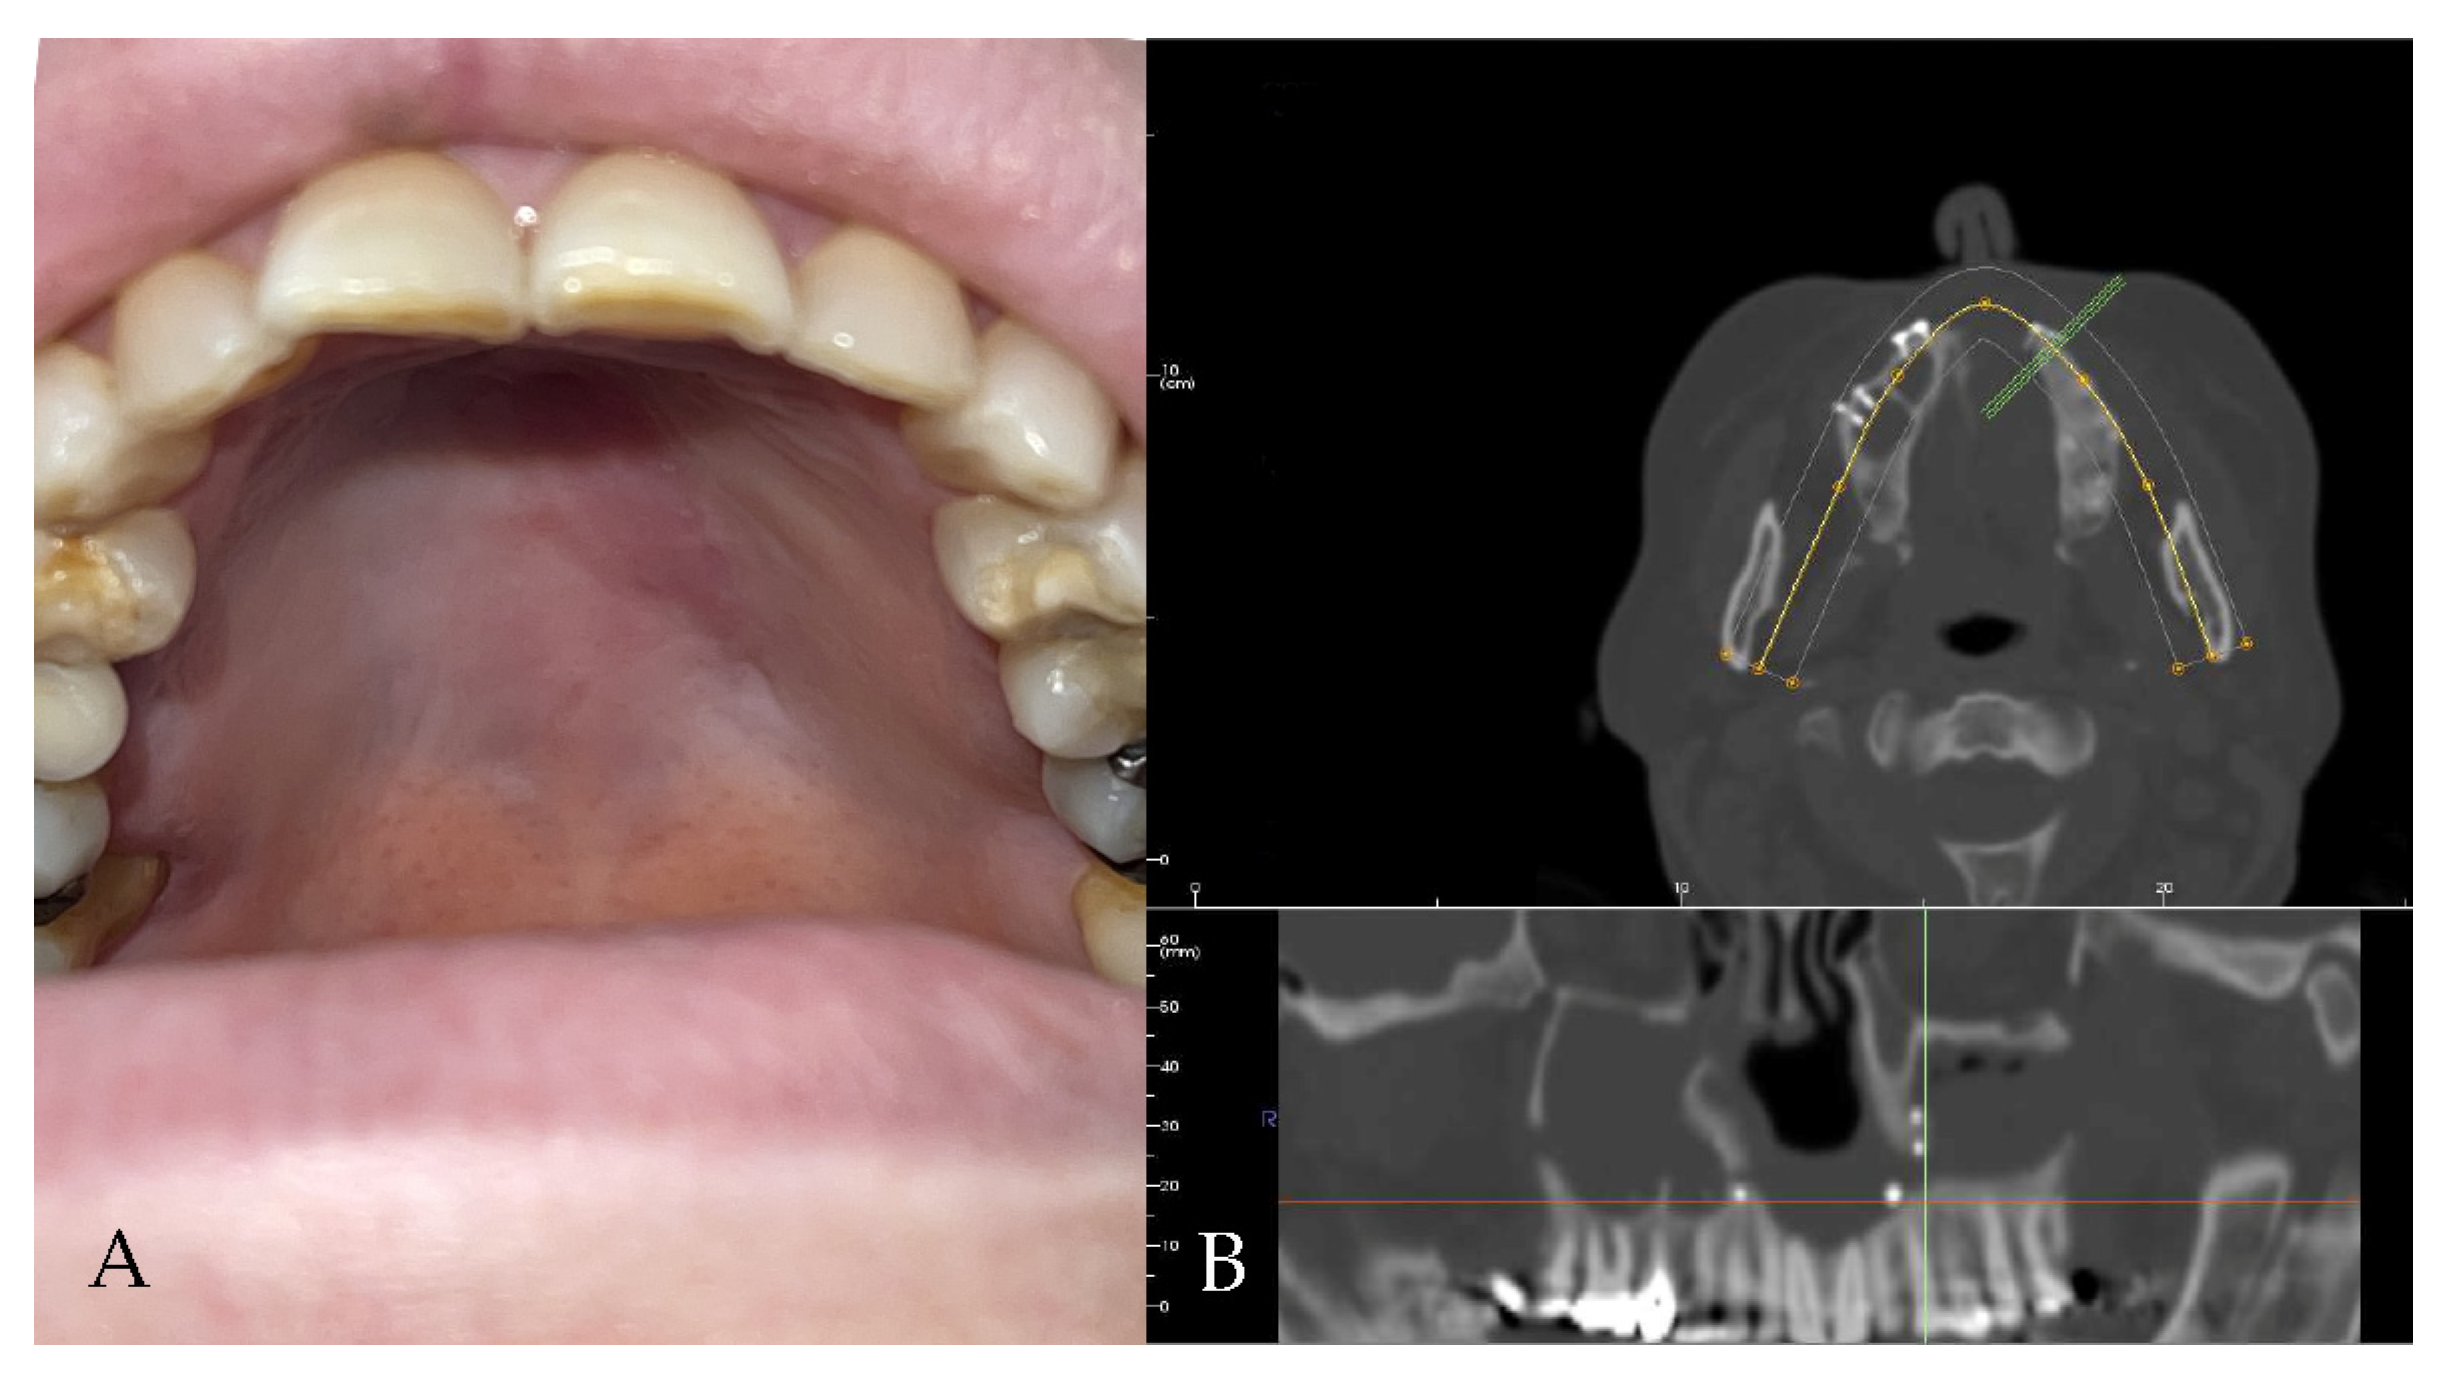

2.2. Case 2

A 52-year-old male patient came to our attention in 2017, presenting with a palatal/oro-nasal fistula measuring 3.5 cm in diameter along the major axis, with atrophic soft tissues surrounding the lesion (Ia according to the Okay et al. classification [14]). The patient had already been treated in 2015 in another center using a palatal local flap with no success and was then treated with an obturator. At the clinical and radiographic examination (Figure 4), a wide oro-nasal communication with exposure of the nasal cavity and septum was observed, leading to speech disturbances, rhinolalia, and eating difficulties.

Figure 4. (A) Clinical presentation of the oro-nasal communication. In inset A, it is possible to appreciate the visibility of the nasal septum. (B,C) Radiographic and 3D reconstruction using InVivo6® and Anatomage Table EDU vers.8® (Santa Clara, CA, USA) software. DICOM files were imported in InVivo6® (Santa Clara, CA, USA) software to obtain the axial, cross, and panorex sections. Afterwards, the DICOM files were imported into Anatomage Table EDU vers.8® (Santa Clara, CA, USA) to obtain the 3D rendering.